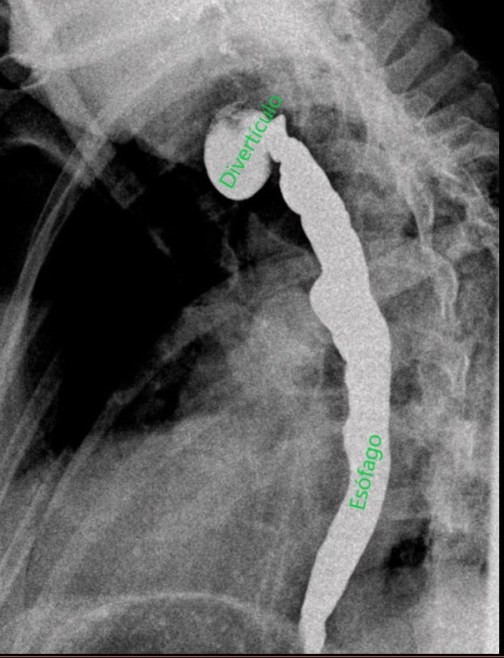

A la paciente se le realizó también un estudio esófago-gastroduodenal (EGD) para su diagnóstico. Se obtuvieron imágenes del esófago mientras que la paciente bebía contraste baritado, observándose el divertículo esofágico (KJ). Comenzamos el estudio en bipedestación (imágenes 6 y 7), después tomaremos imágenes en prono, imagen 8.

Imágenes en OPI en bipedestación donde se observa el paso de contraste por el esófago y una imagen sacular: divertículo esofágico

Imagen 8 en OAD en prono donde se observa el paso de contraste por el esófago.